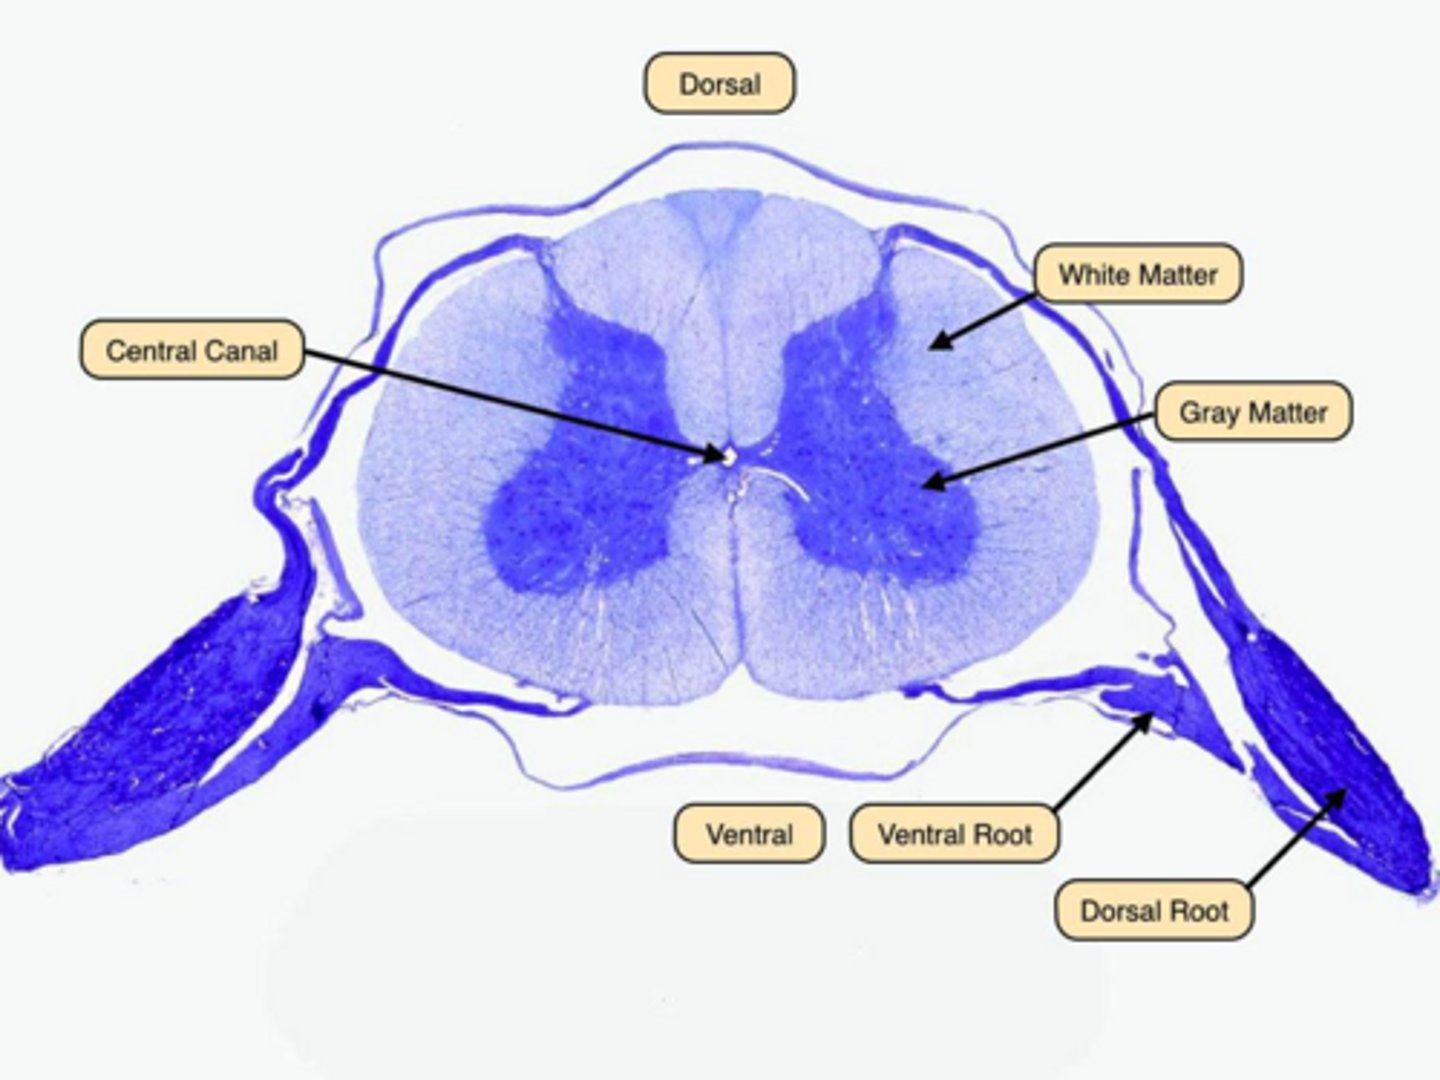

What is the difference between gray matter and white matter?

Gray matter contains cell bodies and dendrites, while white matter contains myelinated axons.

What is the difference between dorsal and ventral roots?

Dorsal: sensory input; Ventral: motor output.

Gray matter: cell bodies and dendrites; White matter: myelinated axons.